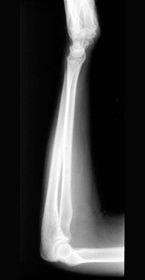

| Lateral Elbow | The elbow is elevated above the level of the shoulder radial head anterior to coronoid - should be superimposed capitulum too proximal to trochlea radial tuberosity seen - hand is pronated |

| Lateral Elbow | Elbow is depressed below the level of the shoulder radial head superimposed by coronoid capitulum too distal to medial trochlea |

| Lateral Elbow | the distal wrist is elevated hand is pronated because you can see the radial tuberosity - should not see that |

| Lateral Elbow Evaluation Criteria | ANATOMY: distal humerus, proximal forearm, entire elbow joint CRITERIA: humeral epicondyles are superimposed radial tuberosity is invisible (if visible the hand is pronated) half of the radial head superimposed by coronoid process Elbow is flexed 90 degrees to see/not see fad pads 3 concentric arcs visible POSITIONING: CR perpendicular @ lateral epicondyle |